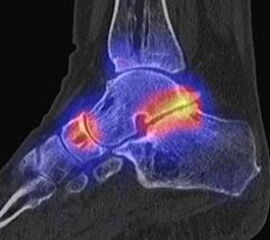

In Abbildung 3.4. ist ein typisches Beispiel für ein symptomatisches Os trigonum dargestellt.

Zum Lesen der Bildbeschreibung und zur Vollansicht bitte das Bild anklicken. Bild: H. C. Rischke

Bei der Differenzialdiagnose von Impingement-Syndromen am Sprunggelenk kann das SPECT/CT den Ort der Symptome- verursachenden Stressreaktion darstellen 32. Eine typische Ursache für ein posteriores Impingement kann ein Os trigonum sein. Scherkräfte im Bereich der Synchondrose eines Os trigonum lösen hypermetabole Stressreaktionen aus. Die Exzision des Os trigonum stellt eine erfolgreiche Therapie dar, sodass der Befund eines szintigraphisch aktivierten Os trigonum den Erfolg einer chirurgischen Therapie vorhersagen kann 3334.